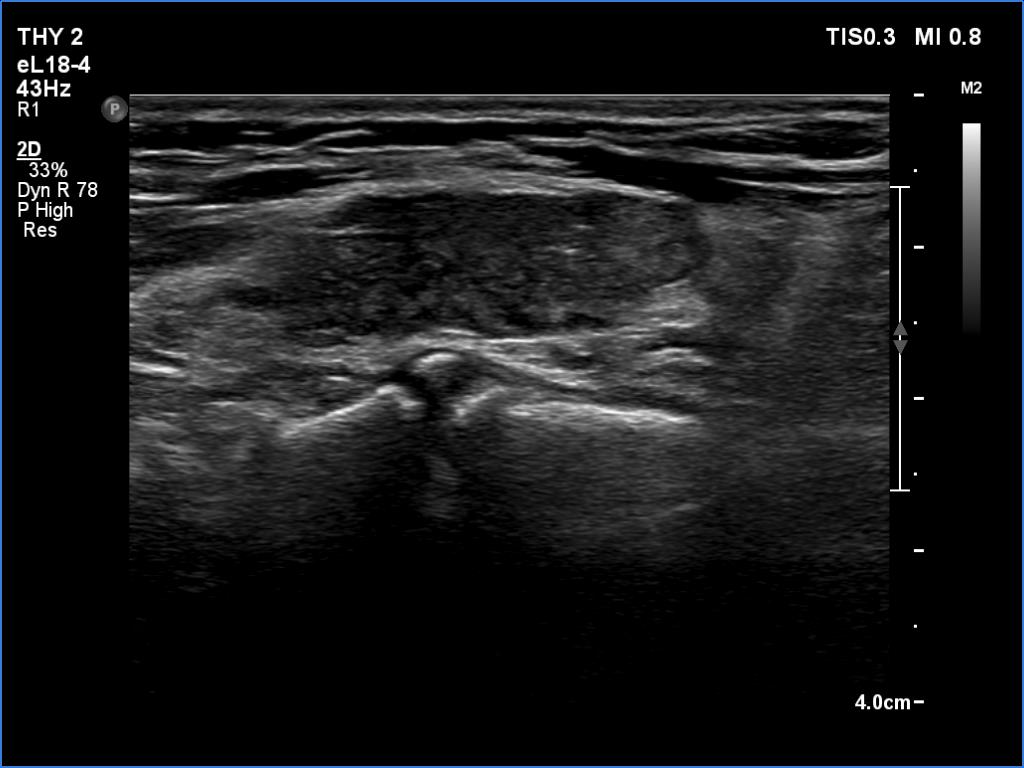

Follow-up investigation 6 months after first visit (ultrasonographic picture 5)

Left lobe, longitudinal scan. This pattern is much less worrying regarding the echogenic granules.